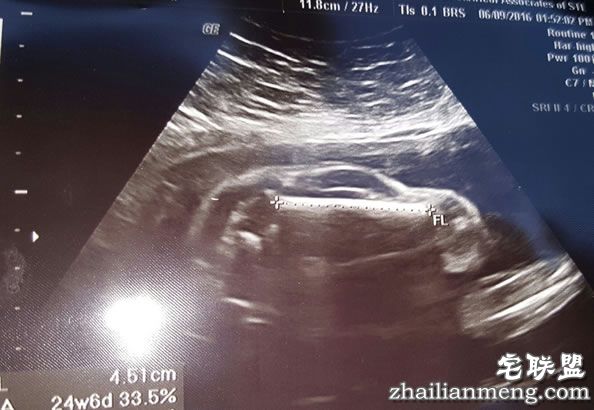

近日国外有位网友分享了一张神奇的跑车照片,是他怀孕的妻子做产前超声波检查时的照片。照片中,几乎看不出胎儿的轮廓,反而很像是一辆跑车,而这也让准爸爸兴奋地说,我老婆怀了一台跑车!

这张照片,短短3天就吸引了超过450篇评论。这张超声波照片中,胎儿的形状神似一辆跑车,可以很清楚地分辨前、后轮,甚至连车窗也有。而这张这片也让网友们疯了,下面也出现许多搞笑留言。